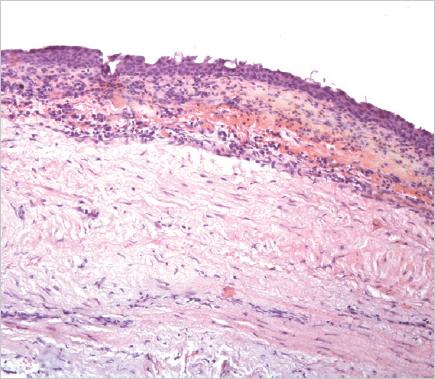

Histological examination of the removed paraurethral cyst was performed (Fig. 6–8).

Fig. 8.The wall of the paraurethral cyst, surgical material. Hematoxylin-eosin staining, ×100. Foci of epithelial lining atrophy are determined

Рис. 8.Стенка парауретральной кисты, операционный материал. Окраска гематоксилином и эозином, ×100. Определяются очаги атрофии эпителиальной выстилки